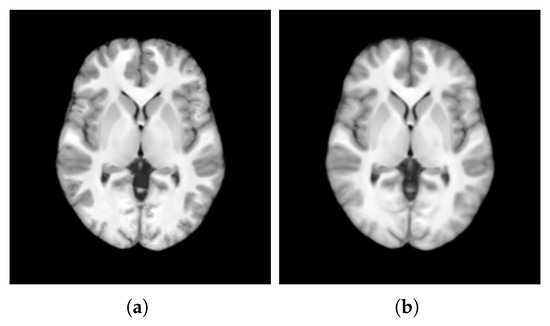

- The unbiasedness of the template structure computed with versus without incorporating weights.

- The quality of template intensity using patch-based estimation versus voxel-based averaging.

4.1. Unbiasedness of Template Structure

4.2. Quality of Template Intensity